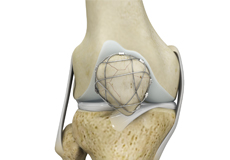

Ligaments are tough bands of tissue that connect one bone to another bone. The ligaments of the knee stabilize the knee joint. There are two important groups of ligaments that hold the bones of the knee joint together, collateral and cruciate ligaments.

Collateral ligaments are present on either side of the knee. They prevent the knee from moving too far during side to side motion. The collateral ligament on the inside is called the medial collateral ligament (MCL) and the collateral ligament on the outside is called the lateral collateral ligament (LCL).

Cruciate ligaments, present inside the knee joint, control the back-and-forth motion of the knee. The cruciate ligament in the front of the knee is called anterior cruciate ligament (ACL) and the cruciate ligament in the back of the knee is called posterior cruciate ligament (PCL).